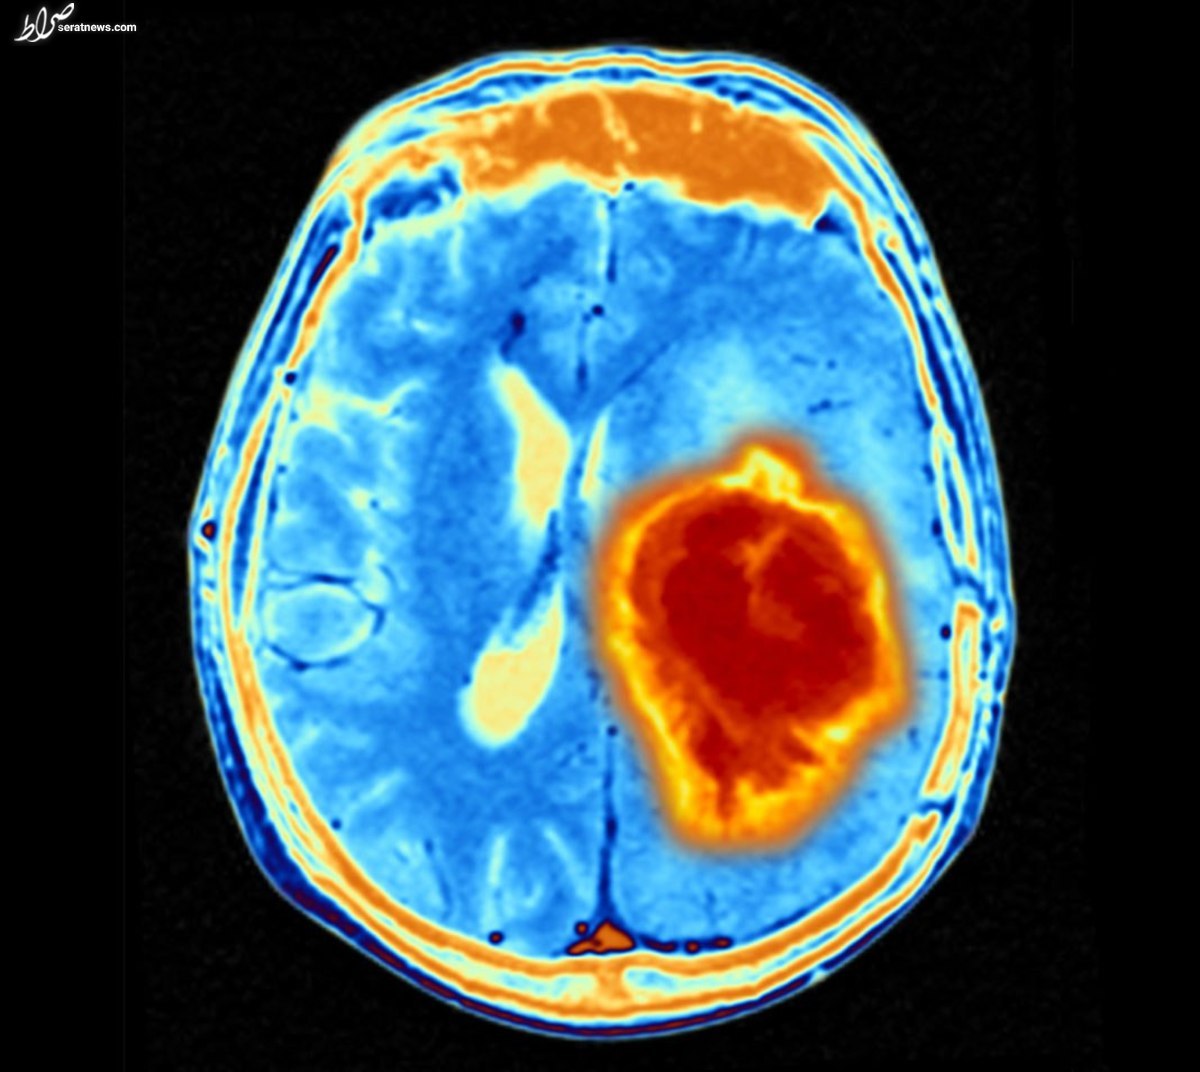

درمان هدفمند تومور‌های مغزی با سلول‌های بنیادی مهندسی شده

درمان هدفمند با سلول‌های بنیادی مهندسی شده برای گلیوبلاستوما به بقای طولانی‌مدت موش‌ها منجر شد.

به گزارش پایگاه خبری صراط به نقل از ستاد توسعه علوم و فناوری‌های سلول‌های بنیادی؛ گلیوبلاستوما‌ها (GBMs) تومور‌های بسیار تهاجمی مغز و نخاع هستند که درمان آن‌ها چالش‌برانگیز است، زیرا بسیاری از دارو‌های سرطانی نمی‌توانند از سد خونی مغزی عبور کنند.